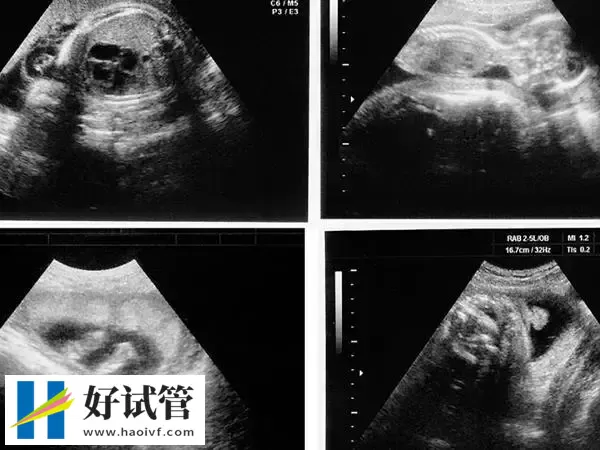

移植第38天孕囊的大小在3cm左右,此时B超下观察胎芽在1.5cm左右,因为移植38天相当于已经正常怀孕8周了,所以这个时期就不能按照孕囊大小计算了,需要按照胎芽或者头臀径计算。孕8周时胎儿长到1.66厘米,胎形已定,可分出胎头、体及四肢,胎头大于躯干。B超可见胎囊约占官腔1/2,胎儿形态及胎动清楚可见,并可看见卵黄囊。

- 8周:1.66厘米此时通过B超能清晰看见胎儿形态及胎动,胎囊约占官腔1/2,可看见卵黄囊;